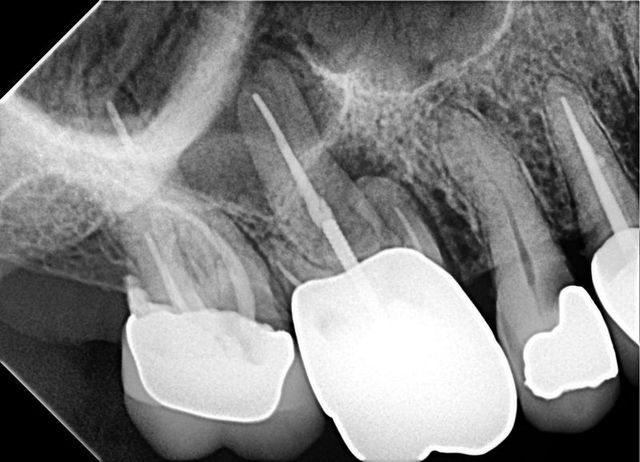

El diagnostico Endodóntico debe valerse de todas las herramientas disponibles a nuestro alcance. Ciertos casos requieren de estudios o pruebas diagnosticas mas especializadas que permiten darnos un panorama mas exacto del estado de salud o enfermedad de estructuras anatómicas que no son posible evaluar clínicamente.

Casos como la siguiente radiografía no permitía un diagnostico acertado, los signos clínicos y síntomas del paciente no eran claros. Se decidió enviar un estudio tomográfico dental (CBCT) donde se logro localizar una Lesión de gran amplitud, provocada por una infección, localizada alrededor de las raíces del Primer molar y una fractura en la furca (zona de unión de las raíces) con compromiso oseó.

Con la información completa se refirió al paciente para exodoncia

Diagnóstico endodoncia